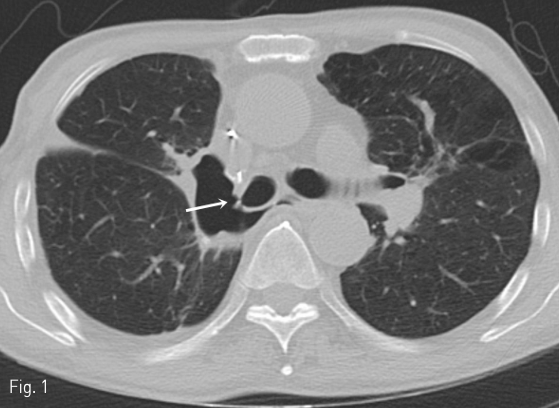

수술 3주 후에 시행한 흉부 CT에서 수술부위의 bronchial stump에 작은 틈새가 보였다 (Fig. 1). 그로부터 11일 뒤 시행한 CT에서 stump의 틈새가 더욱 커지고 (axial dimension: 8 mm) 흉강과 교통을 보이는 기관흉막루가 형성되었다 (Fig. 2).

Fig 1

Axial chest CT reveals a tiny defect (white arrow) with adjacent pleural space air in the bronchial stump of the resected right upper lobe, representing bronchopleural fistula.